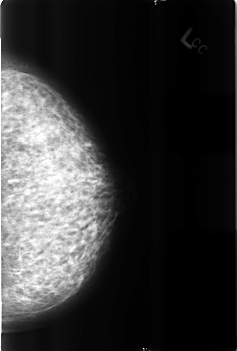

B_3183_1.RIGHT_MLO

B_3183_1.LEFT_CC

LEFT_CC LINES 4552 PIXELS_PER_LINE 3072 BITS_PER_PIXEL 12 RESOLUTION 50 NON_OVERLAY

LEFT_MLO LINES 4512 PIXELS_PER_LINE 3024 BITS_PER_PIXEL 12 RESOLUTION 50 NON_OVERLAY

RIGHT_CC LINES 4624 PIXELS_PER_LINE 3064 BITS_PER_PIXEL 12 RESOLUTION 50 OVERLAY

RIGHT_MLO LINES 4488 PIXELS_PER_LINE 3056 BITS_PER_PIXEL 12 RESOLUTION 50 OVERLAY

FILE: B_3183_1.RIGHT_MLO.OVERLAY

LESION_TYPE CALCIFICATION TYPE LUCENT_CENTER DISTRIBUTION N/A

ASSESSMENT 2

SUBTLETY 3

PATHOLOGY BENIGN_WITHOUT_CALLBACK

FILE: B_3183_1.RIGHT_CC.OVERLAY